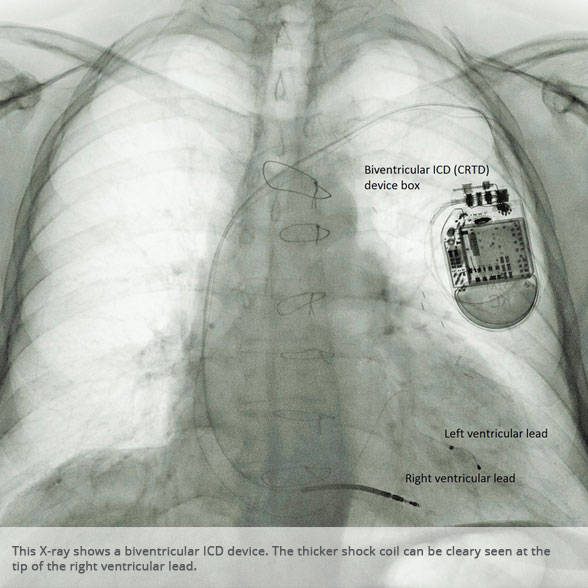

Biventricular ICD (CRTD) Biventricular ICD (CRTD)

Biventricular ICD (CRTD) device Biventricular ICD (CRTD) device

Above: Slideshow containing X-rays of common medical procedures.

Although not all patients universally respond to bi-ventricular pacing (or cardiac resynchronisation therapy/CRT), patients with more advanced dys-synchrony tend to experience remarkable improvement. Bi-ventricular ICDs have the additional benefit of recognising life threatening arrhythmia and deliver both fast pacing bursts or shocks to restore normal heart rhythm.

ICDs

ICDs are used to treat life threatening arrhythmia emerging in the main pumping chambers of the heart (the ventricles). They are offered to patients deemed at risk of such ventricular arrhythmia (primary prevention), for example those who require intervention as a result of significant ventricular scarring after heart attacks, or patients who have been fortunate to survive a cardiac arrest (secondary prevention).

There are established risk stratification algorithms we use to detect patients who may benefit from ICD treatment. ICDs will deliver both fast pacing bursts and shocks to terminate life threatening arrhythmia.